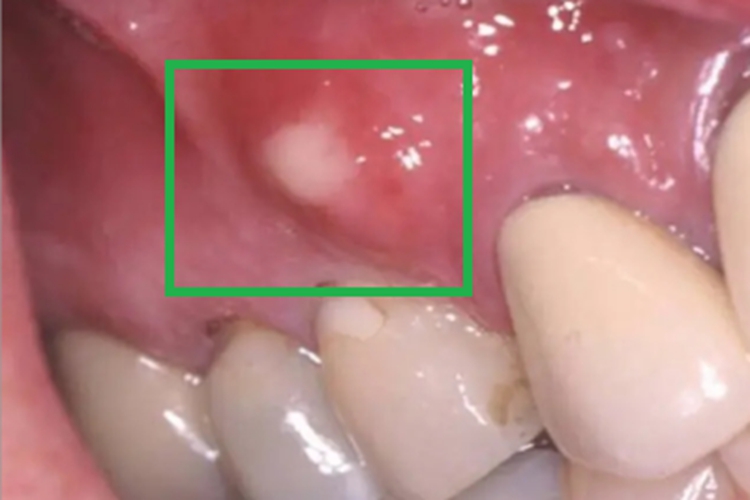

急性坏死性龈口炎累及牙龈时,局部可出现异常凸起的疙瘩,顶端发白,大小不一,形状并不规则,同时牙龈边缘及龈乳头红肿,患处牙龈易出血,疼痛明显,口内有特殊的坏死性口臭。